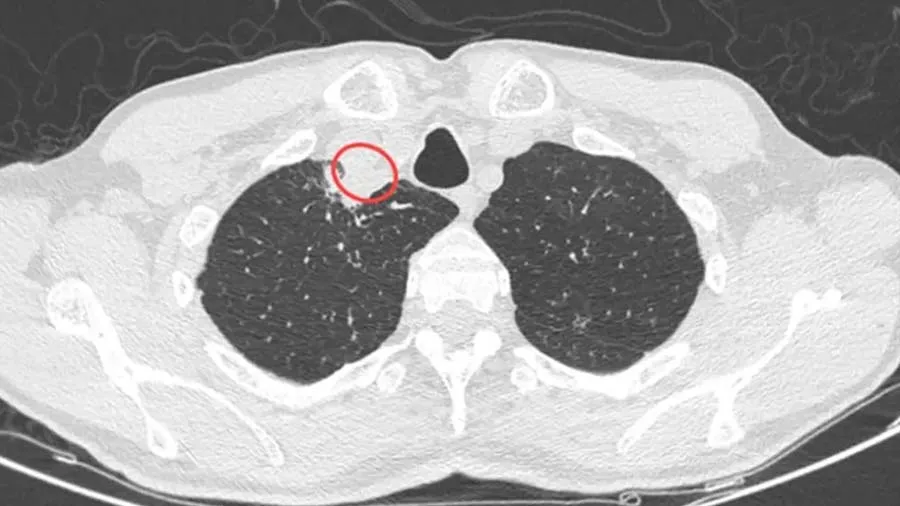

સીટી સ્કેન કરવા પર તેના ગળામાં એક પેરાટ્રાચેયલ ફોલ્લી નજરે પડી. તપાસ બાદ ડૉક્ટર્સે એ ફોલ્લી હટાવી દીધી અને ટેસ્ટ માટે એક સેમ્પલ, વિશ્વ આરોગ્ય સંસ્થા (WHO)ના રેફરન્સ એન્ડ રિસર્ચ ઓન ફંગી ઓફ મેડિકલ ઇમ્પોર્ટન્સના સહયોગી કેન્દ્ર પર મોકલ્યા છે. સંક્રમિત વ્યક્તિને ડાયાબિટીસ, HIV સંક્રમણ, કિડનીની બીમારી કે પછી કોઈ બીજા પ્રકારની જૂની બીમારી નહોતી. દુનિયામાં છોડથી માણસમાં થયેલા પોતાની જાતના સંક્રમણના કેસના કારણે ચોડ્રોસ્ટેરિયમ પરપ્યૂરિયમ બતાવવામાં આવી રહ્યો છે.